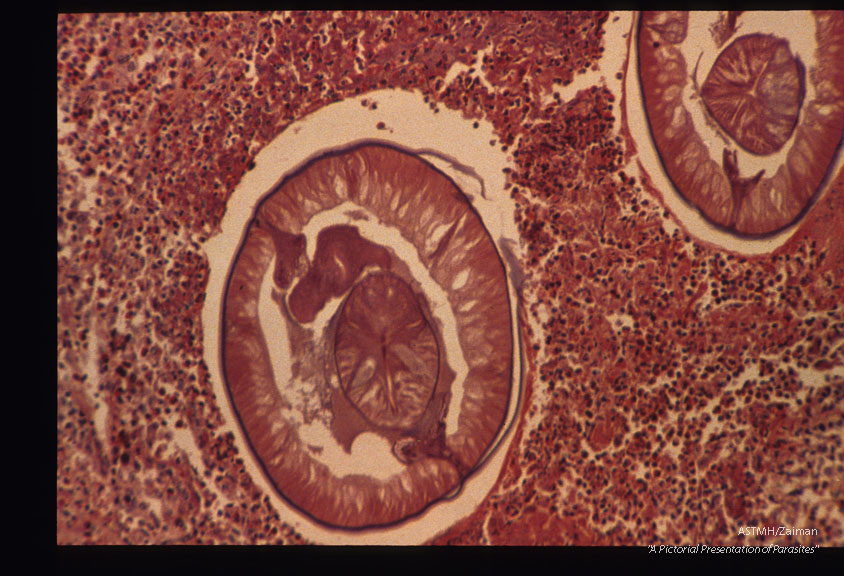

Another case from Holland. Low and high power magnifications of worms in stomach wall.

Anisakis

Description: Another case from Holland. Low and high power magnifications of worms in stomach wall.